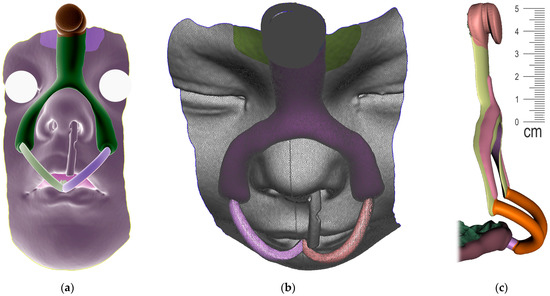

The appliance to be designed and manufactured in the example case of craniofacial disorder (PRS) was supposed to achieve an effect comparable to the effect of the conventional Tübingen Palatal Plate (TPP) in Figure 3. With the original TPP with wire, the infant also learns to suck milk, so it can be in place basically around the clock, which would not be possible with our new design. For simplification, the new 3D-printed two-part appliance described in this article has not been named in any special way and is referenced as “TPP” as well later in the text. The manufacturing of conventional TPP is a complicated process and typically, the laboratory provides two alternatives with different spur angulation as a rough anticipation of suitable proportions. Old TPP is made from physical intraoral impressions and CT segmentation is also not implemented in the process.

The principle of therapeutical effect in this appliance is the propulsion of the root of the tongue forward and the consequent opening of the collapsed airway in the corresponding portion of the pharynx. The scheme in Figure 4 shows three main parts of the appliance, where the pressure of the oropharyngeal spur to propel the tongue has alveolar anchorage with extraoral support. The 3D-printed appliance is removable, with one extraoral part and one intraoral.

Only the parts in contact with the appliance were relevant from the CT and were exported in STL format and later aligned with the STL output from the intraoral scanning, as is shown in Figure 5a,b.

Figure 3. Conventional design of Tübingen Palatal Plate (TPP) made by laboratory technician with metallic hooks for extraoral pull and safety metallic wire in the body of oropharyngeal spur: (a) Lingual view; (b) Palato-lateral view. Scale is in cm.